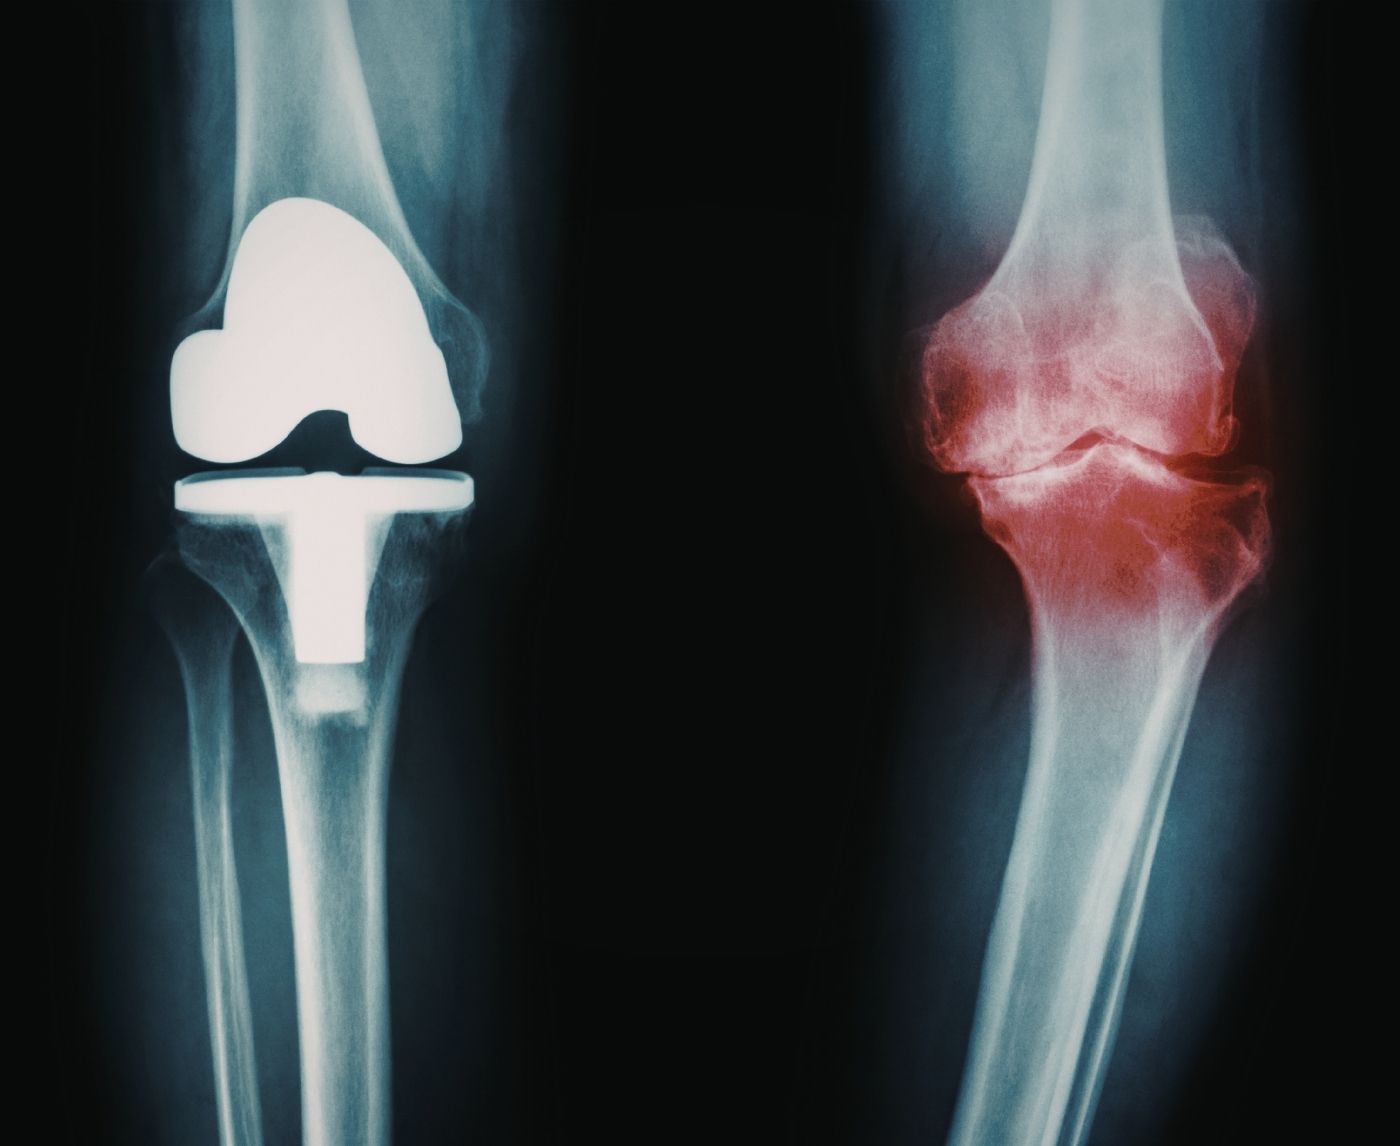

What’s Actually Happening Inside the Joint

Inflammation is supposed to protect you. After an infection, immune cells release signaling proteins called cytokines. These help eliminate bacteria and repair tissue. In reactive arthritis, that protective response overshoots.

Fragments of bacterial proteins can linger in the body even after antibiotics wipe out active infection. In genetically susceptible people, those fragments appear to trigger ongoing immune activity. The joints become collateral damage in an immune system that’s still on high alert.

It doesn’t mean your body is broken. It means your immune response is enthusiastic, sometimes too enthusiastic.

For some, this inflammatory cascade fades naturally. For others, it needs medication support to calm things down.

Treatment: Calming the Fire Without Blaming the Body

Treatment focuses on two things: making sure the original infection is gone and reducing joint inflammation.

If testing reveals persistent chlamydia, antibiotics are prescribed again. If the infection is cleared, attention shifts entirely to inflammation control. Nonsteroidal anti-inflammatory drugs are frequently the initial preference. In more serious cases, short courses of corticosteroids or other therapies that change the immune system may be an option.